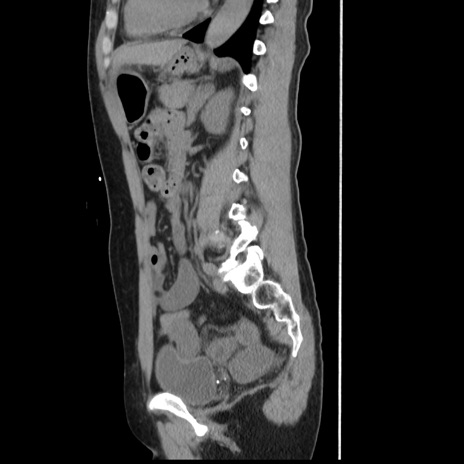

横断像

【症例】 50歳代女性

【主訴】 腹痛

【現病歴】前日生レバーを食べた。今朝に排便あり。 昼前に突然発症の腹痛を生じ、当院救急外来を受診した。

【既往歴】 子宮筋腫にてで子宮全摘後

【身体所見】 意識清明、腹部:平坦、軟、下腹部やや左を中心に圧痛・反跳痛あり、筋性防御あり

【データ】WBC 7800、CRP 0.07